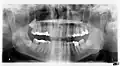

Панорамная рентгенограмма, показывающая дефект Стафне (отмечен стрелкой)